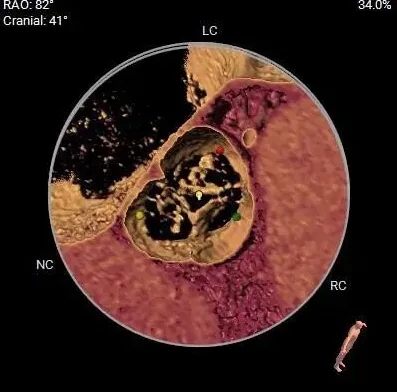

主动脉根部测量

ANNULUS

周长径23.7

周长径24.2

34.9mm&32.1mm&34.3mm

周长径31.2

周长径41.7

瓣上结构测量

周长径26.9

周长径25.2

三叶瓣重度钙化

敞口流出道

钙化主要分布于左、无瓣叶上

STJ及升主未见明显扩张

冠脉风险评估

Left Coronary 8.0mm

Right Coronary 18.7mm

左冠开口较低,结合瓦氏窦大小,预估冠脉风险相对较低